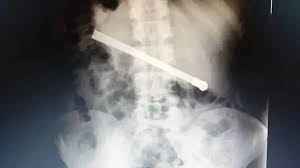

El jueves 2 de enero, hubo una fuerte discusión donde la acusada terminó apuñalando a su papá. Fue el hermano de Jenifer quien lo encontró gravemente herido y dio aviso a la Policía. Según informaron las fuentes oficiales, ella nunca escapó del lugar, admitió haber sido la autora del crimen y aseveró haber sufrido severos maltratos, agresiones físicas, explotación infantil y abusos sexuales por parte de su padre. Este punto será clave para las autoridades del Tribunal debido a que las pericias determinarán si es verídica la denuncia.